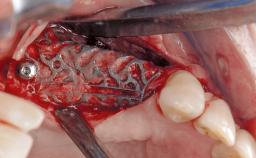

Resective Surgical Treatment of Peri-Implantitis Including Implantoplasty

In this case, Myroslav Solonko, Ignacio Sanz Sánchez and Mariano Sanz present a treatment that aims to eliminate exposed implant threads by modifying the implant surface, converting a moderately-rough surface into a smooth surface.

A 63-year-old male patient was referred to the post-graduate periodontal clinic of the Complutense University of Madrid for the treatment of peri-implantitis. According to the patient’s record, all his maxillary teeth had been extracted ten years previously due to severe periodontitis, and a full-mouth implant-supported restoration on eight implants was placed. No supportive periodontal therapy was provided apart from occasional check-ups by the restorative dentist.